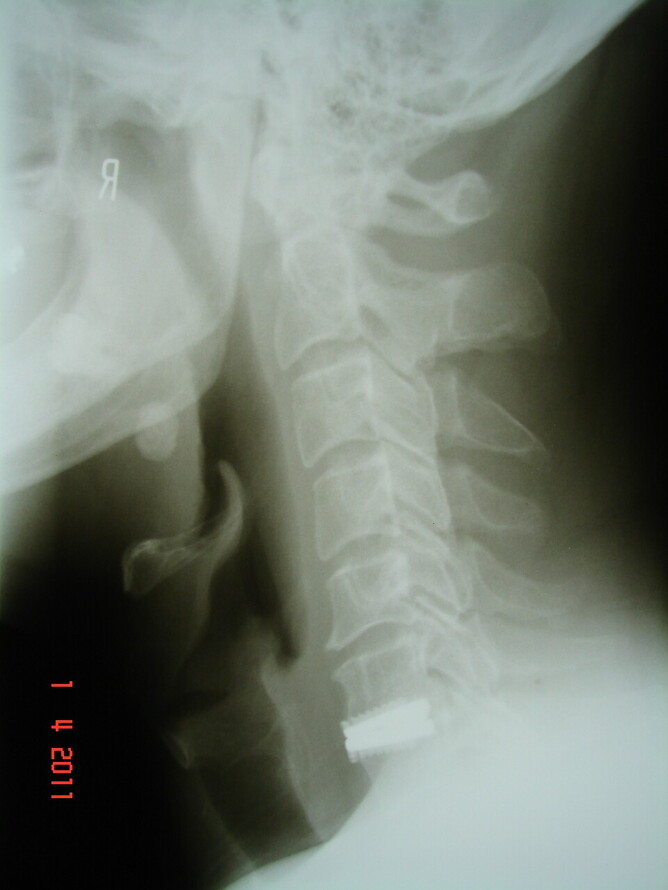

We now offer a service where we will review the presenting complaint and the imaging (Xrays usually) and correlate the symptom to the reports and results of the imaging. We will attempt to answer the questions that the patient has in regard to the report from the specialist and correlate the symptom to the imaging.

2). A referral plus explanation. The patient has a consultation and examination made in the clinic. An appropriate referral is made. Several days later, when the report from the radiology clinic is sent to us, we consult with the patient, explain what is seen on the imaging and discuss appropriate management.